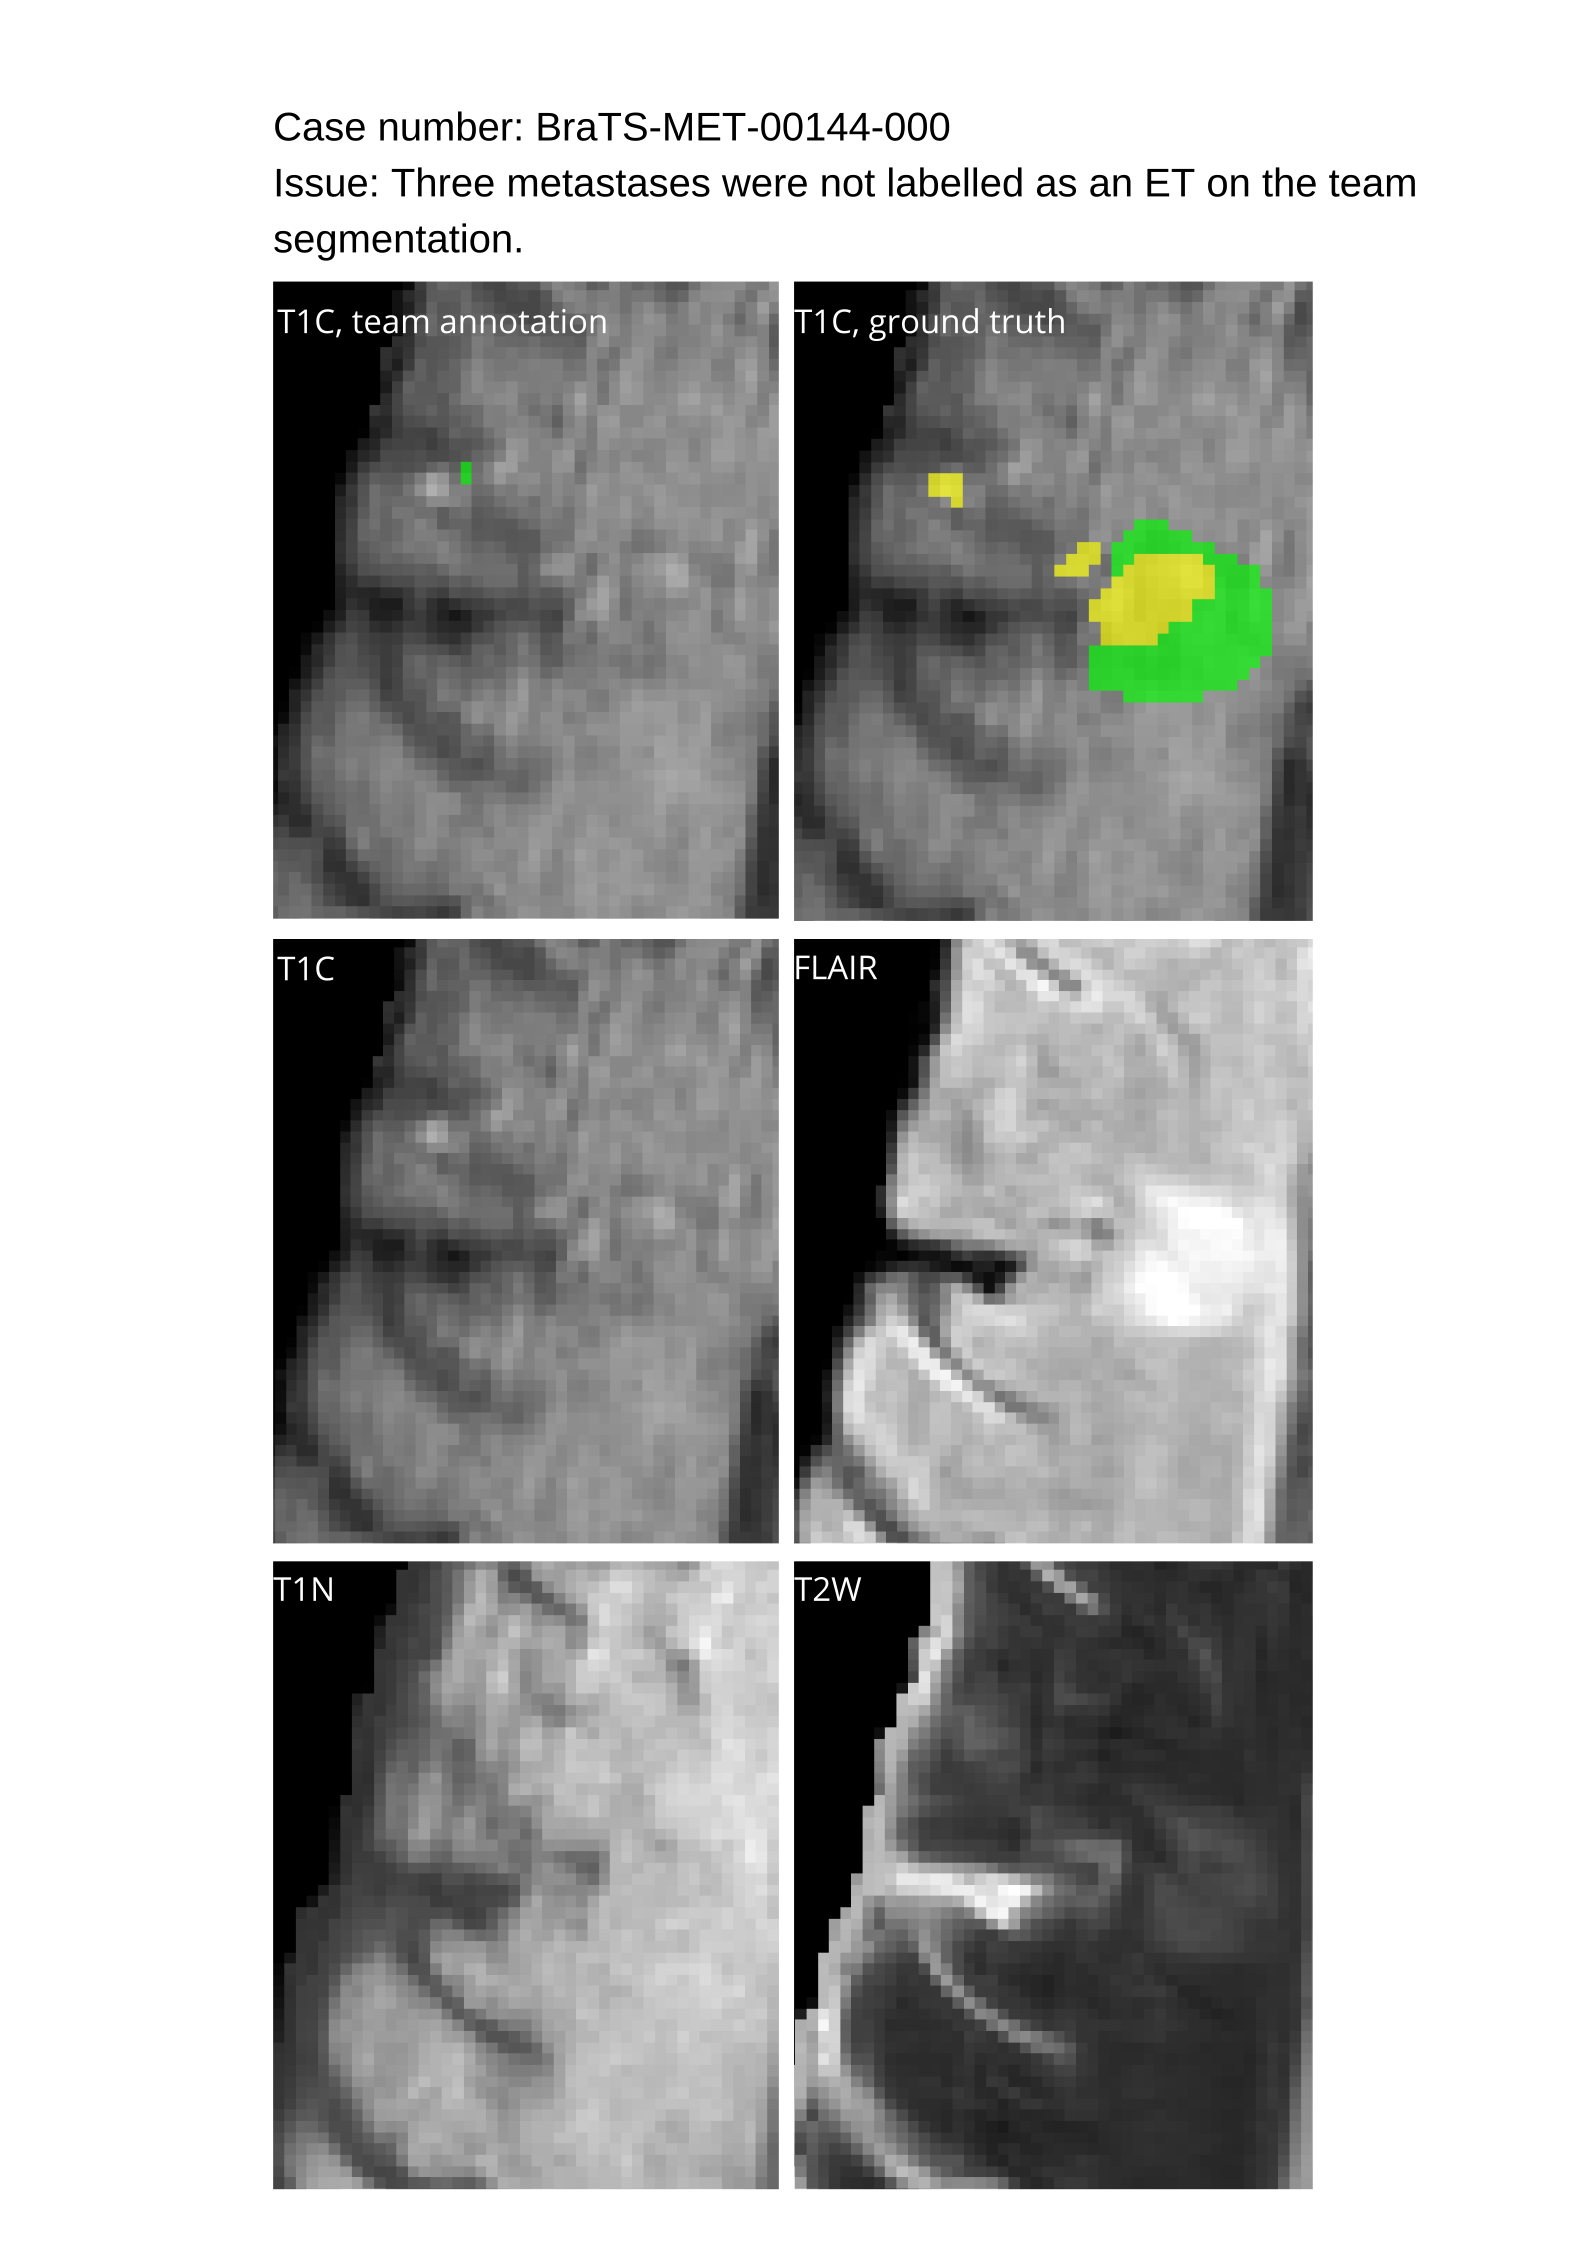

4.9 Common Errors of Automated Segmentations

Based on observations from previous BraTS challenges, common errors in automated segmentations were identified. The most typical errors in the current challenge included:

1. 1.

Automated algorithms missing small metastases. Enhancing metastasis was fused using the minority voting algorithm to aggregate all enhancing tumor voxels identified by the three algorithms. However, many small metastases were missed and were manually segmented by neuroradiology attendings.

2. 2.

Segmentation of white matter changes from microvascular disease. Peritumoral edema segmentations were checked by neuroradiology attendings and modified.

3. 3.

The segmentation of non-enhancing lesions that have intrinsic T1 hyperintensity. Voxels with intrinsic T1 hyperintensity were manually removed from ET segmentations.

These insights led to specific adjustments in the annotation process to enhance accuracy.